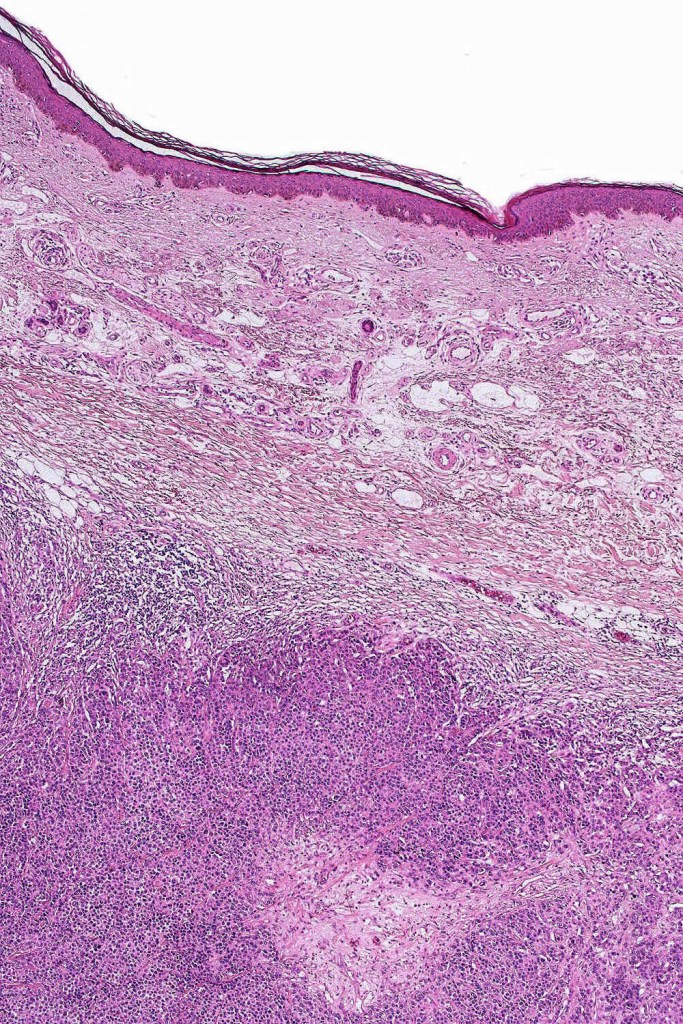

•Extremely rare often amelanotic, high-grade variant (based on the majority of documented cases representing metastases. The biological potential of primary tumors with rhabdoid features is uncertain owing to the paucity of reported cases)

•Metastases & recurrent disease>>primary tumors

•Characterized by pleomorphic tumor cells with large eosinophilic, hyaline globular inclusions and eccentric vesicular nuclei containing prominent nucleoli, mitoses often conspicuous

•Very sparse melanin pigment may be identified

In this example, rhabdoid change accounted for only a small component of the tumor. IHC is S100